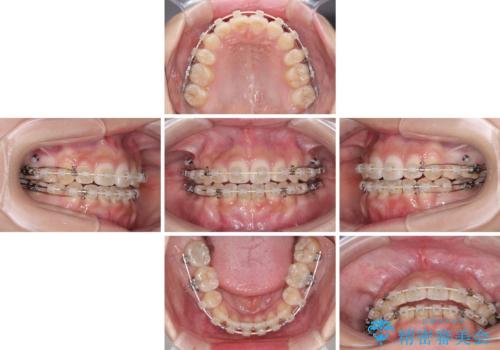

- 矯正装置

- 審美装置

- 1年6ヶ月

舌のトレーニングをしっかりと行ってくださり、1年半という非常に短い期間で仕上げることができました。